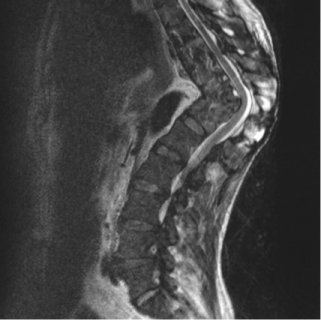

A 44 years-old Romanian man presented at our Emergency Department with productive cough, fever with chills, profuse sweating, and chronic dorsal pain. He referred previous history of tuberculosis with progressive dorsal gibbus deformity treated only with antibiotics several years before in his country. The patient underwent blood tests and chest X-ray that confirmed the suspect of recurrent pulmonary tuberculosis. The physical examination assessed no neurologic deficits. After being isolated, the patient underwent full spine MRI that showed the consequences of previous Pott’s disease extended from T8 to T12 vertebral levels. As shown in the figure, D11 vertebral body was completely collapsed causing a segmental kyphosis with a Cobb Angle of 82,12º and posterior spinal cord tenting with no signal changes. A TC-guided biopsy confirmed the microbiological diagnosis. The patient was treated for the recurrent pulmonary tuberculosis with a combination of antibiotic drugs with complete healing after 40 days of therapy.

The MRI findings show the potential severe deformity associated with Pott disease. The risks associated with a surgical correction of the segmental kyphosis were unacceptable due to the absence of neurological impairment and the relative stability of his deformity.

The severity of dorsal hyperkyphosis shown in figure is a very rare occurrence in industrialized countries and this radiological finding shows the potential consequences of untreated Pott disease.